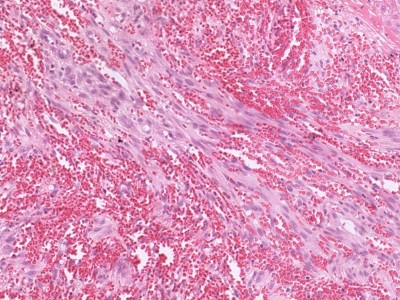

PA:Histologisch beeld varieert nauwelijks

tussen de verschillende subtypen. De histologie is wel afhankelijk van het ziektestadium.

'Plaque'

stadium: vasculaire proliferatie tot in de diepe dermis en soms de subcutis.

Spoelcellen (met expressie van endotheelmarkers) nemen de plaats van het

dermale collageen in. Er liggen groepjes erytrocyten buiten de vaten

(erytrocytenextravasatie), en in gedilateerde spleetvormige vaatruimten

('slit-like' ruimten). Het endotheel is gezwollen, er is endotheliale celatypie, en soms is een erytrocyt omsloten door één endotheelcel (erytrocyten phagocytose). Er

is depositie van hemosiderine. Tevens een mononucleair infiltraat (lymfocyten en plasmacellen). Vroege laesies kunnen lijken op granulatieweefsel, met veel, wijde capillairen, grote endotheelcellen, en een diffuus chronisch ontstekingsinfiltraat (lymfocyten, plasmacellen, macrofagen).

Meestal afwezigheid van atypie, mitosen en pleiomorfisme;

komt soms voor in late stadia.

![Histologie Kaposi sarcoom (click on photo to enlarge) [source: Kevin Kwee / Afdeling Pathologie MUMC] Histologie Kaposi sarcoom](../../../pacoupes/thumbnails/Kaposi-sarcoom-1.jpg) |

![Histologie Kaposi sarcoom (click on photo to enlarge) [source: Kevin Kwee / Afdeling Pathologie MUMC] Histologie Kaposi sarcoom](../../../pacoupes/thumbnails/Kaposi-sarcoom-2.jpg) |

|

ingescande coupe (zoom) |

Bron

hoge resolutie PA-foto's: Kevin Kwee en Afdeling Pathologie MUMC. Klik

op de afbeelding om in te zoomen.